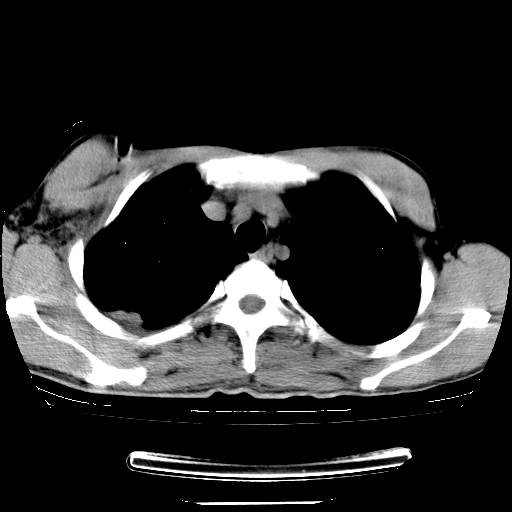

以下是引用dyqct在2008-4-29 8:43:00的发言:[br][br] 支持右侧胸腔包裹性积血。闭式引流管是不是插的太深了?

以下是引用zjzjr在2008-4-29 14:11:00的发言:[br]支持右侧胸腔包裹性积血。闭式引流管是不是插的太深了?胸腔引流,引流管快进入纵隔了.